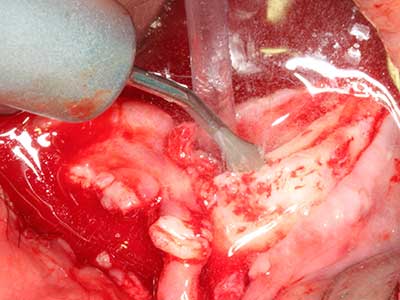

Indication: Preparation near nerves

Indication: Apical resection

When surgical procedures are performed on bone in the immediate vicinity of sensitive structures such as blood vessels or nerves, rotary instruments pose a significant risk of iatrogenic injury. Piezoelectric devices can be helpful for preparation of bone covers and removal of hard tissue close to nerves, particularly for exposure of nerves after iatrogenic injury but also during nerve lateralization for resective and reconstructive procedures or implant placement (Fig. 17-20). Light contact between the piezotip and the nerve does not generally result in damage but proceeding incautiously with saw-like motions or attachments where a residual bone substrate remains may cause temporary or even permanent nerve damage. However, the risk of damage is considered to be substantially lower than when using saws or milling instruments (Pereira, Gealh et al. 2014).